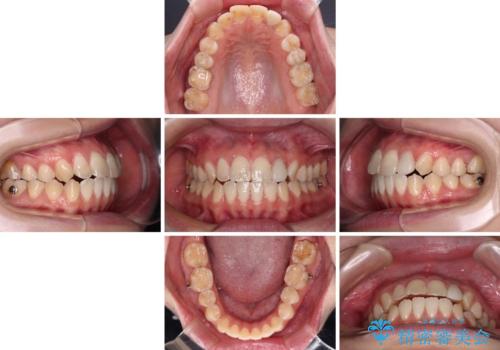

開咬を治す インビザラインによる矯正治療

- 上下前歯の開咬を気にして来院された患者様です。

開咬はインビザラインを用いると有意に改善ができるため、インビザラインによる矯正治療を行うこととしました。

途中1年8ヶ月ほど来院されず、久しぶりの来院後は治療が面倒とのことで、前歯の叢生や隙間に不十分な点が残った状態での終了となりました。